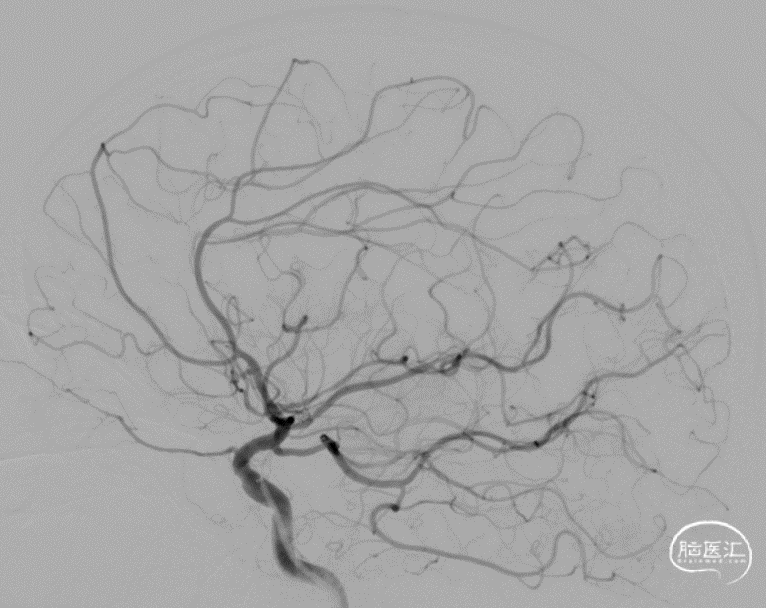

最后工作位造影和正侧位造影,右侧大脑中动脉区域血流恢复,灌注满意。

术后CT无出血,术后患者未诉不适,无新发神经功能症状及体征,继续予以抗栓、强化降脂、调节血糖等治疗。